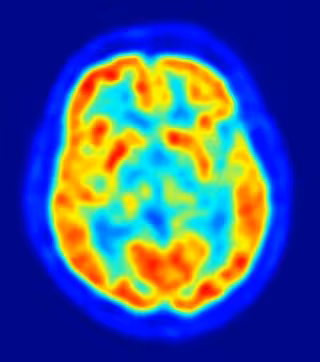

Los investigadores de Nottingham utilizaron imágenes de resonancia magnética funcional (fMRI) para comparar los cerebros de 35 voluntarios sanos con los de 38 pacientes esquizofrénicos. Los resultados mostraron que mientras que la mayoría de los individuos sanos fueron capaces de hacer este cambio entre las regiones, los enfermos de esquizofrenia eran menos propensos a cambiar a la utilización de su corteza frontal.

La corteza insularidad y frontal forman un sensible bucle "prominente", en el que la ínsula debe estimular la corteza frontal, mientras que a su vez la corteza frontal debe inhibir la ínsula, pero se detectó que en los pacientes con esquizofrenia este sistema se ve seriamente comprometido. Los resultados sugieren que la detección de la falta de una influencia positiva de la ínsula a la corteza frontal mediante fMRI podría tener un alto grado de valor predictivo en la identificación de pacientes con esquizofrenia.